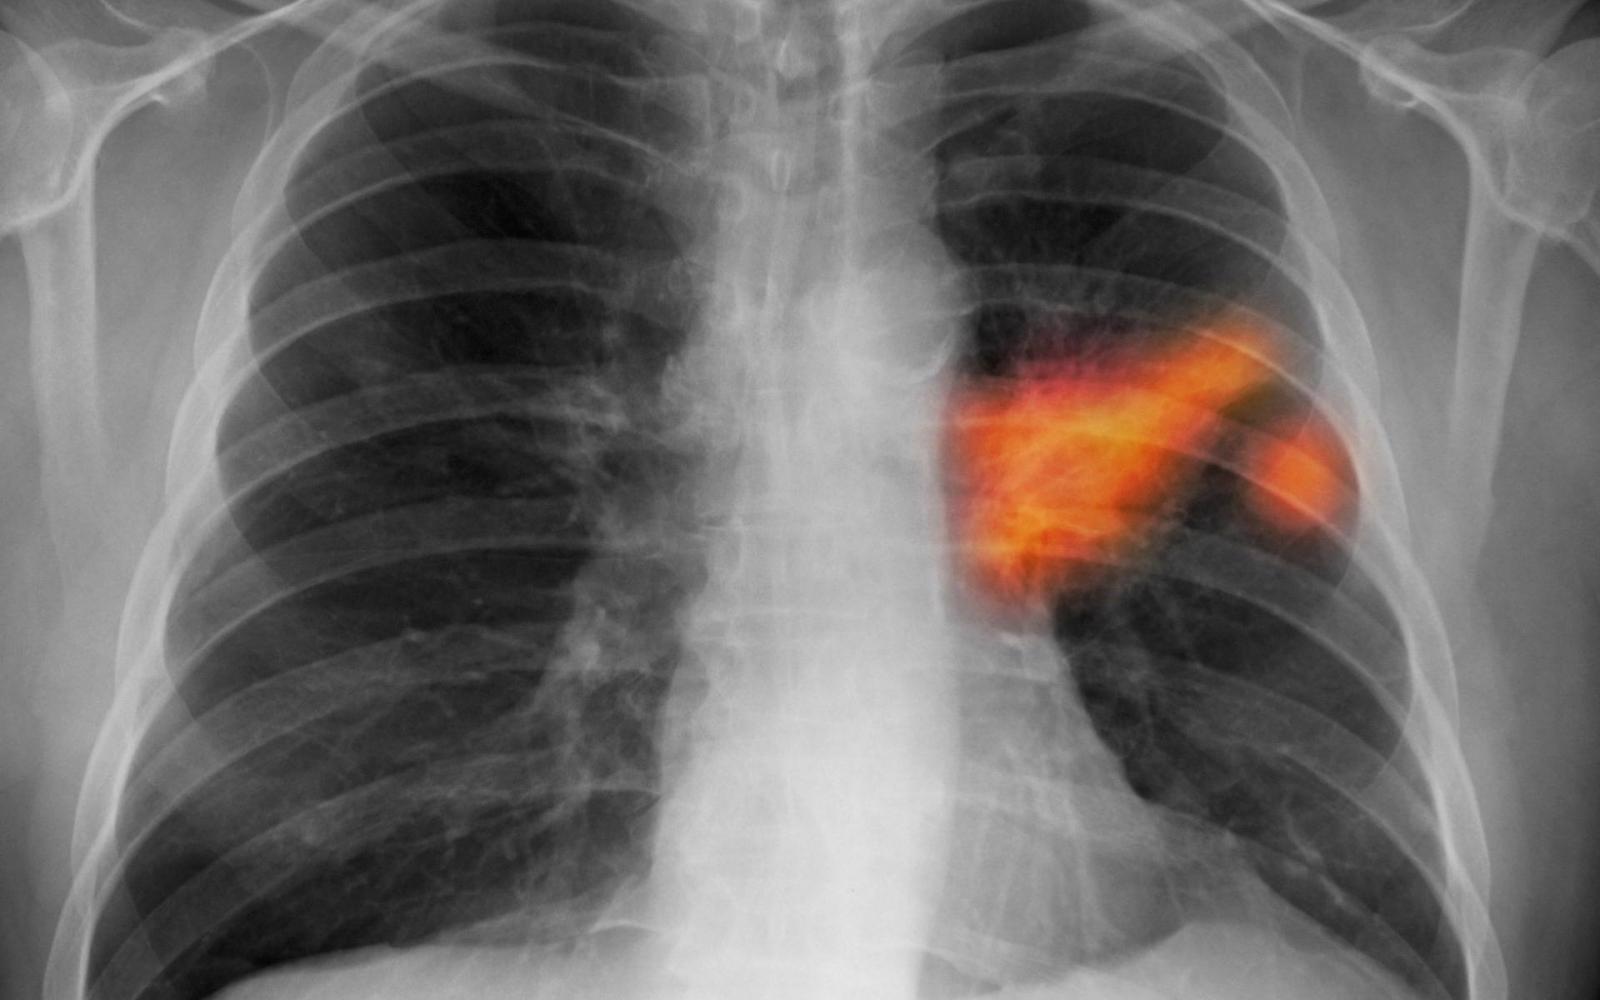

Carlo La Vecchia, a Milánói Egyetem tudósa vezette nemzetközi kutatócsoport a 27 európai uniós ország és Nagy-Britannia adatait elemezte. Részletes adatokat közöltek a hat legnagyobb lakosságú országra - Franciaországra, Németországra, Olaszországra, Lengyelországra, Spanyolországra és Nagy-Britanniára - vonatkozóan és a tíz leggyakoribb rákfajtát figyelembe véve. Ezek a gyomor, a bél, a hasnyálmirigy, a tüdő, a mell, a méh és méhnyak, a petefészek, a prosztata, a húgyhólyag rákos megbetegedése és a leukémia.

„A rák a szív- és érrendszeri betegségek mellett a második leggyakoribb halálok Európában. Bár megjósolhatóan sok rákfajta esetében idén csökken a halálozási arány, a betegség okozta halálesetek abszolút száma a népesség öregedése miatt továbbra is emelkedik” – mondta Paolo Boffetta, a kutatás társszerzője, a Bolognai és a New York-i Egyetemen is dolgozó szakértő.